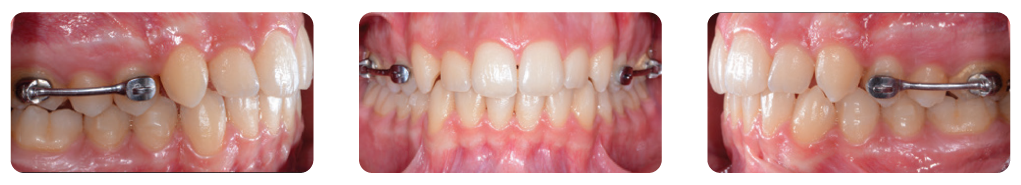

Overlay of initial (white) and post-treatment (green) occlusion in virtual setup viewer. Buccal grip points were planned on the upper right canine and first premolar, upper left canine and first molar, lower right first premolar, and lower left canine and second premolar. In addition, 0.1 mm of interproximal reduction (IPR) was planned at each contact point from the mesial surface of the upper right first molar to the mesial surface of the upper left first molar, and from the mesial surface of the lower left second premolar to the mesial surface of the lower right second premolar. IPR was used to reduce the proclination of both arches and achieve a good anterior relationship with normal overjet and overbite. Aligners were changed every two weeks. After the 12th planned set of aligners, four more were added to the series to refine the result (pictures below).

The clear aligner therapy lasted eight months. Treatment Results Post-treatment records indicated a satisfactory outcome after four months of Carriere Motion Appliance with fulltime Class II elastic wear and eight months of clear aligner therapy.